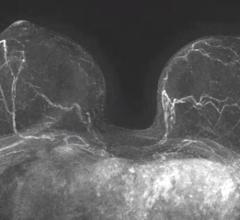

Despite decades of progress in breast imaging, one challenge continues to test even the most skilled radiologists ...

August 3, 2022 — Structural differences in lung airways between men and women may be the cause of differences in chronic ...